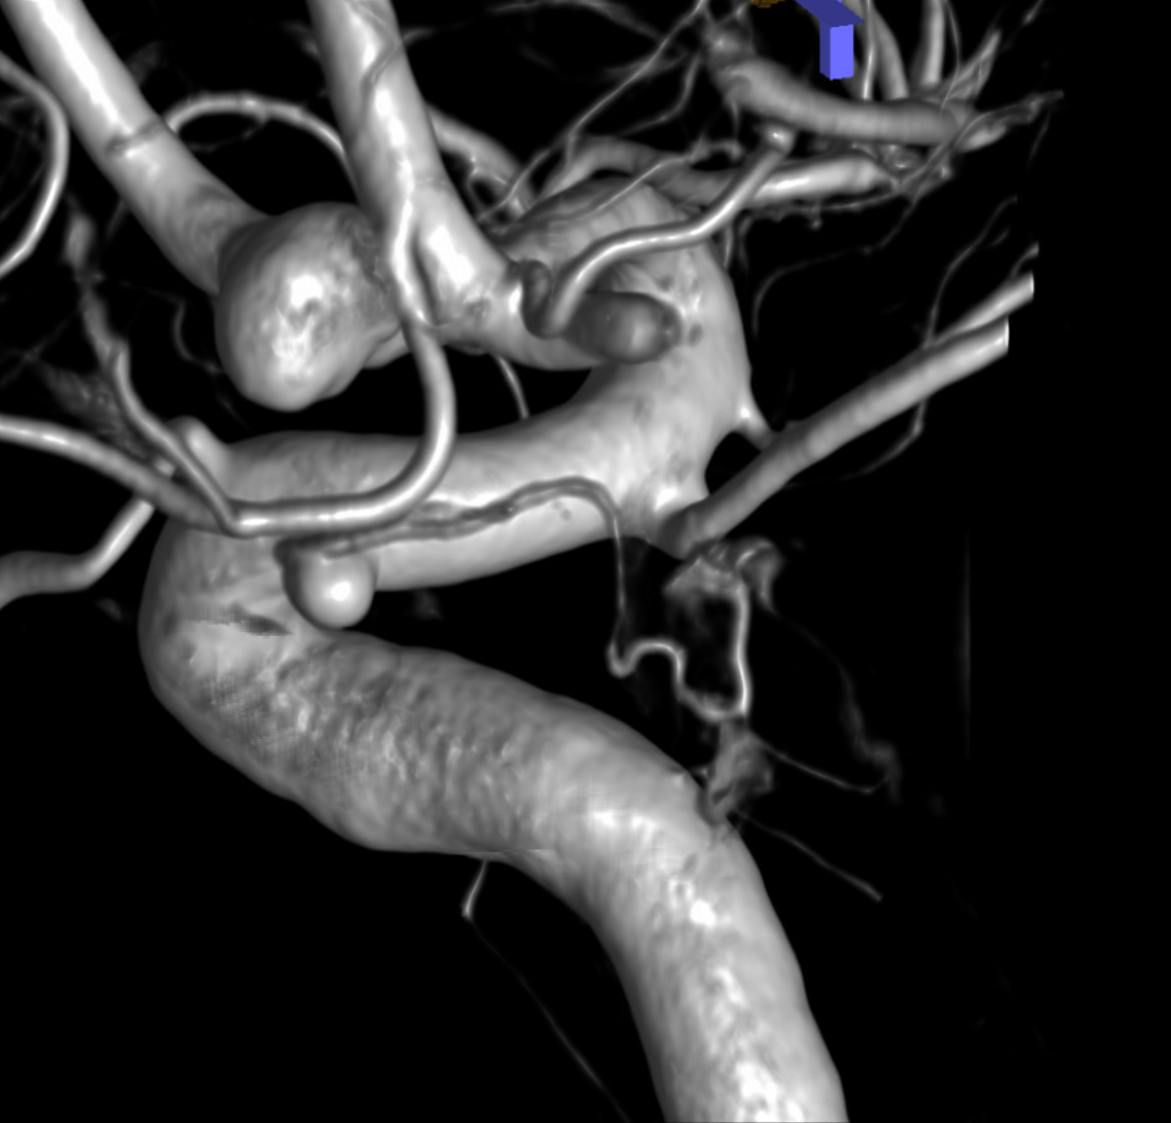

Pure arrowless images — easier to steal…

Of course, there is an aneurysm here — the branch point camp would point out how this larger than usual branch is a setup for aneurysmal formation. Naturally…

Below is a Volume Rendered typical arrangement — a slender (but still large by its own standards) superior hypophyseal supplies the stalk (and anterior pituitary), while inferior hypophyseal from MHT supply the posterior pituitary.